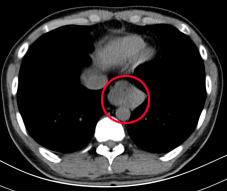

CT可以发现食管裂孔扩大,胃上移到胸腔,形成食管裂孔疝